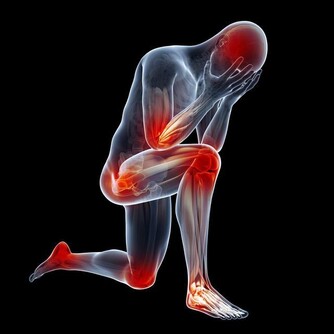

現代醫學界發現,免疫力與衰老有密切關係,免疫力減退是導致衰老的因素之一。並且,醫學界還越來越傾向於,提高免疫力能夠抑制腫瘤發生,預防腫瘤復發和轉移,對於癌症患者有重大意義。

而免疫系統,是人體自身的防禦機制,它最大的作用在於識別和消滅外來入侵的異物(包括病毒、細菌等),同時處理衰老、損傷等自身細胞(包括受感染或癌變的細胞),從而保護人們遠離疾病,讓人們保持年輕。

簡單來講,如果把人體比作一個國家,那免疫系統就是一支軍隊,一旦發現入侵者,就會通知T細胞去除掉對方,進而確保人體健康。

所以,免疫力好的人,不容易受到病菌等的感染,身體一年到頭都很少感冒;相反,免疫力不好的人,臉色差不說,還很容易生病,嚴重時有可能引發重大疾病。